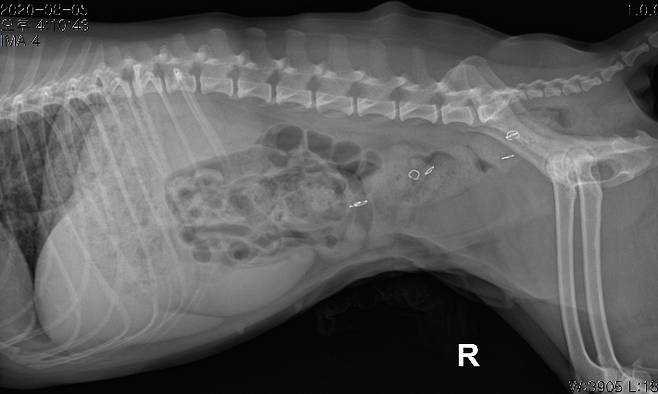

2020년 7월 폼피츠 강아지 앵두(가명)의 경우에도 수술이 잘못되는 피해를 겪었다. 앵두는 피부병 때문에 내원했지만 원장의 권유로 중성화 수술을 받았다. 퇴원한 앵두의 술부가 벌어져 피고름이 나오는 상황에서 원장은 앵두의 생살을 스테이플러로 찍었다.

2주 재입원하고 퇴원했을 때 보호자는 다른 동물병원에서 앵두 피부가 개복됐고 조직이 괴사됐다는 사실을 알았다. 원장이 제거했다던 스테이플러 심도 앵두 몸속에 그대로 있었다. 보호자는 B씨에게 '의료행위상 주의의무 위반'으로 손해배상을 청구해 1심에서 승소했고, 병원 측은 항소했다.